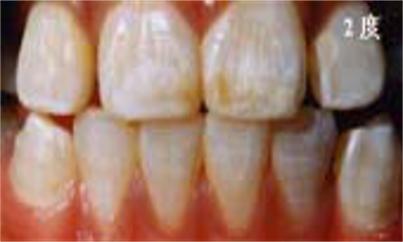

儿童牙齿发育过程中摄入过量的氟会引起氟斑牙:

轻度:白色条纹或斑块,占牙面1/2以下,可出现浅棕色着色。

中度:上中切齿或全口牙整个牙面出现白垩,失去光泽,有明显着色。有的出现小点状凹坑。